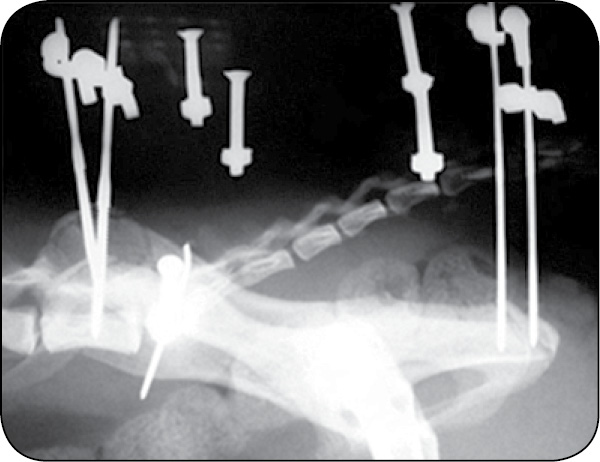

Stabilizatory można stosować w bardziej złożonych konfiguracjach w leczeniu złamań miednicy, gdyż są bardzo przydatne ze względu na problematyczną stabilizację tego obszaru. Można je również łączyć ze stabilizacją wewnętrzną, gdyż ramię dźwigni stabilizatora jest znacznie dłuższe w porównaniu do wewnętrznego implantu (płytki i wkrętu). W przypadku stabilizacji hybrydowej po kilku tygodniach, po wytworzeniu się już kalusa kostnego, stabilizator można usunąć, pozostawiając jedynie wewnętrzne implanty, gdyż będą już wtedy poddawane mniejszym obciążeniom (ryc. 20, 21).